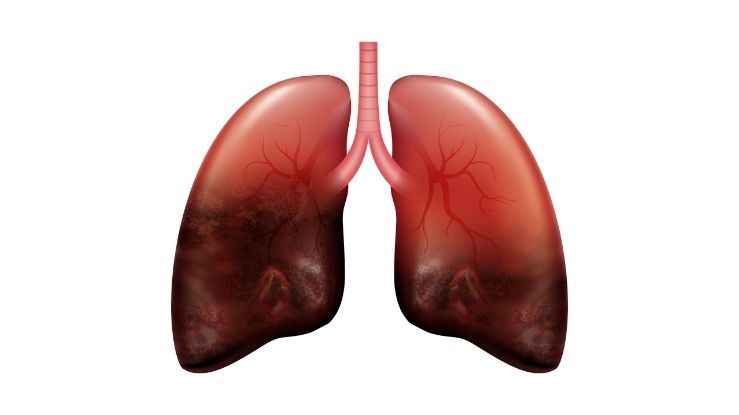

Akciğer kanseri, dünya genelinde en sık görülen kanser türlerinden biridir. Kadınlarda erkeklerde olduğu kadar ciddi bir sağlık sorunu da olası değildir. Akciğer kanserinin seyrinde çeşitli faktörler rol oynar, bu faktörler arasında genetik özelliklerin önemli bir yeri vardır.

Genetik tedavinin akciğer kanseri tedavisindeki rolü için öncelikli olarak genetik yatkınlık ve kanser gelişimi arasındaki dağılımın belirlenmesi gerekmektedir. Birçok çalışma, akciğer kanseri vakalarının %8-14'ünde genetik yatkınlığın etkili olduğunu göstermektedir. Özellikle ailede akciğer kanseri öyküsü bulunan kadınlar, bu kişilerin yakalanma riskine diğer bireylere göre daha dayanıklıdır.

Genetik akciğer akciğer kanseri etkileri, birkaç farklı mekanizma üzerinden açıklanabilir. belirtilerin ilki, DNA'nın doğal büyüme süreci ve anormallikler ile birlikte karşılaşılan hasarları tamir etme yeteneğinin gelişmesidir. Bu durumda, kanserle büyüyen genetik değişiklikler birikir ve kanserin değiştirilmesine zemin hazırlar.

Bunun yanı sıra, genetik akciğer kanseri hastalıklarının sonuçları arasında DNA onarıcı sistemin işlevsizleşmesi de bulunmaktadır. Bazı genetik değişiklikler, DNA hasarı onarım yeteneği bozar ve kanser oluşumu oluşumuna yol açar.

Genetik faktörler ayrıca akciğer kanseri ölümleri ve metastaz yapma özelliklerini de etkiler. Bu nedenle, genetik akciğer kanseri hastalıklarının rolü, sadece bölünmüş gruplarda değil, yayılma sürecinde önemli bir faktördür.